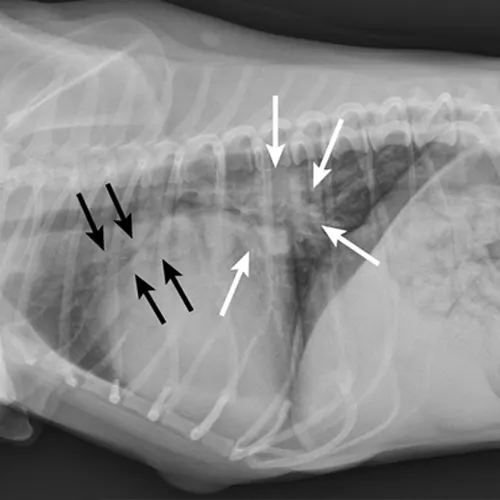

Primary cardiac disease that leads to CHF-related pulmonary edema commonly causes diffuse (perihilar in the dog) or variable (in the cat) interstitial and alveolar patterns. The vertebral heart score (VHS) is an objective method for evaluating the size of the cardiac silhouette (see Steps to Measure VHS). Certain cutoff values are used to determine whether acute respiratory distress is primarily pulmonary or cardiac in origin and to guide initial therapy for stabilization and planning for definitive cardiac or respiratory workup. A VHS <11.4 in the dog can help rule out mitral valve disease–related CHF as a cause for respiratory signs.3 Although an increased VHS can be associated with primary cardiac disease, it is not a specific characteristic in small-breed dogs because of their thoracic conformation.3 In the cat, a left lateral VHS ≤7.9 can reasonably rule out the presence of heart disease.4 Additional radiographic changes associated with primary cardiac disease include left atrial enlargement and pulmonary venous distension (Figures 1 and 2). Pleural effusion can be associated with CHF and primary pulmonary disease. A miliary pattern and/or solitary soft tissue densities in the lungs are indicative of primary pulmonary disease (Figure 3). Hyperinflation of the lung and distinct peribronchial markings are supportive of lower airway disease, although peribronchial markings can be found in the cat with CHF.

Figure 1.

Right lateral thoracic radiograph of a dog that was presented with labored breathing and a moist cough. The patient had a history of a heart murmur, and the breathing pattern was synchronous with increased effort on inhalation. Thoracic auscultation revealed diffuse, soft moist crackles and a 4/6 left systolic heart murmur over the mitral region. Butorphanol and furosemide were administered and the patient was allowed to rest with supplemental oxygen before radiography. Radiographs showed a VHS of 12.5, significant left atrial enlargement (white arrows), and pulmonary venous distension (black arrows) consistent with left-sided heart failure. Mitral valve insufficiency caused by valvular endocardiosis was confirmed with echocardiography.